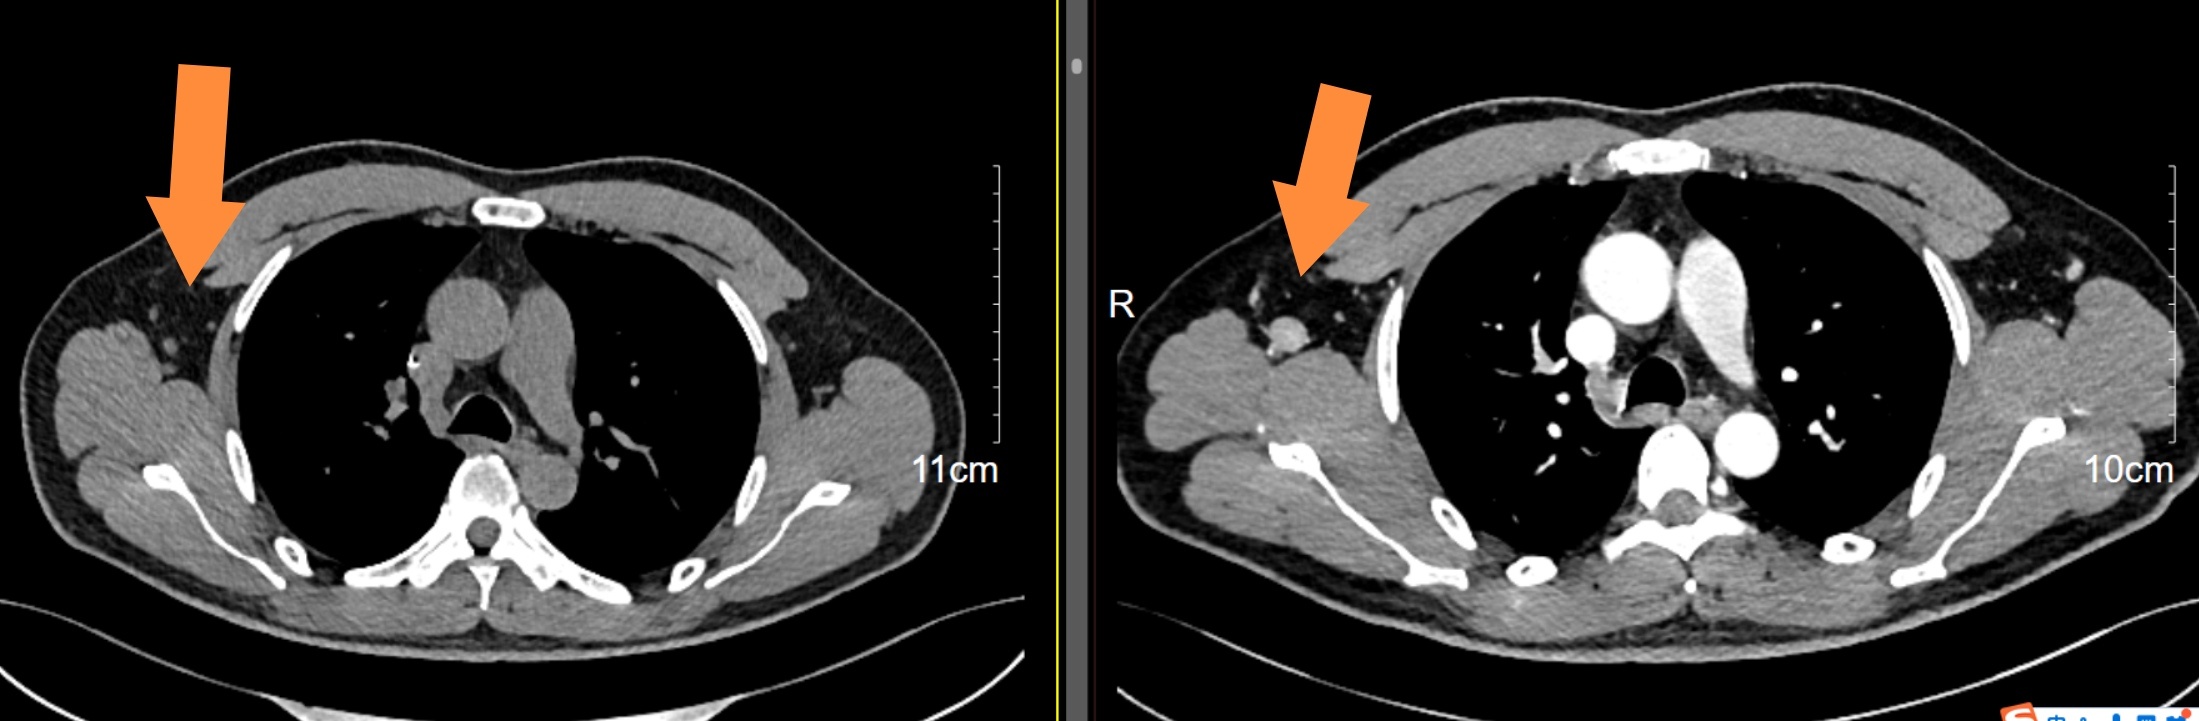

目前2周期化疗后第14天查白细胞低了,中性粒细胞0.6*10*9,打了两次短效升白针(隔天一次),第18天查恢复了,只是睡眠很差,常需要助眠药辅助睡眠,今日今日复查了颈胸腹部CT,大多数病灶都缩小了大概50-70%不等,我还是很欣慰,我是准备4周期后再做PETCT行中期评估。